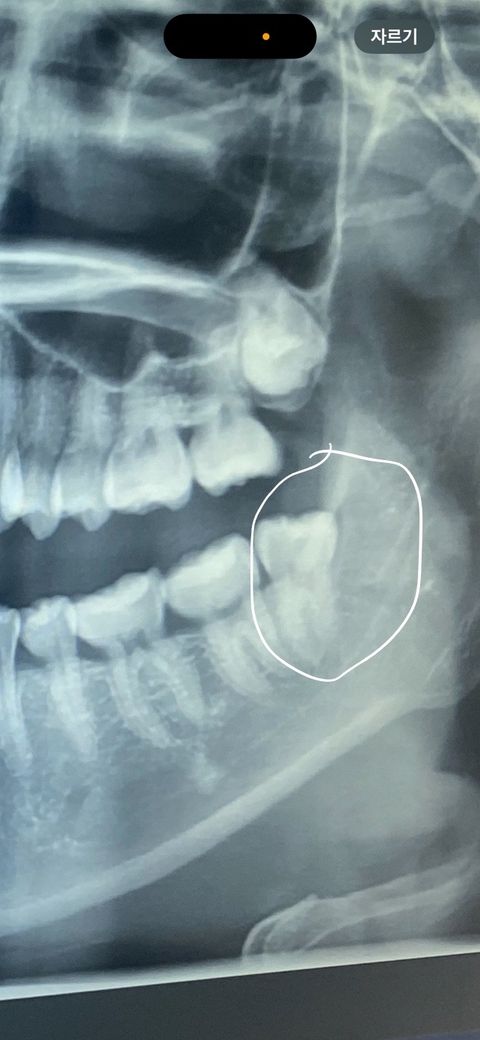

부분 매복사랑니 맞나요? 누워있는 치아는 아니죠?

사진 참고해주세요!!

이거 예전에찍은 씨티?사진인데요

동그라미 친부분이 현재 아래쪽 사진 동그라미 친부분이 맞는걸까요? 부분매복사랑니인가여

부분 매복 사랑니로 분류할 수 있으며 누워있지는 않습니다. 발치는 크게 어렵지 않을겁니다.

비스듬이 누워잇는 치아는 아닙니다. 뒤쪽으로는 잇몸과 잇몸뼈에 살짝 치아가 뭍혀 잇을것같습니다.

사랑니가 잇몸 아래에서 완전히 나오지 않고 일부만 드러나 있는 상태인 경우 부분 매복입니다. 누운 사랑니보다는 발치 난이도가 낮아지는 경향이 있지만, 잇몸을 열어야 할 가능성이 있으며, 사랑니 주변의 염증 상태를 확인하고, 필요한 경우 발치 여부를 결정하길 권합니다.

1. 파노라마 사진입니다.

2. 부분매복에 해당되나 그렇게 깊진 않습니다. 매복 사랑니보다는 수월하게 뺄 수 있을 것 같습니다.

사진으로 봤을 경우에는 부분적으로 매복되어 있는 것이 맞습니다 뒤쪽으로 매복되어 있는 경우 발치 난이도가 상대적으로 볼 수 있습니다 자세한 확인을 위해서 치과에서 진료를 받아 보는 것을 권해드립니다